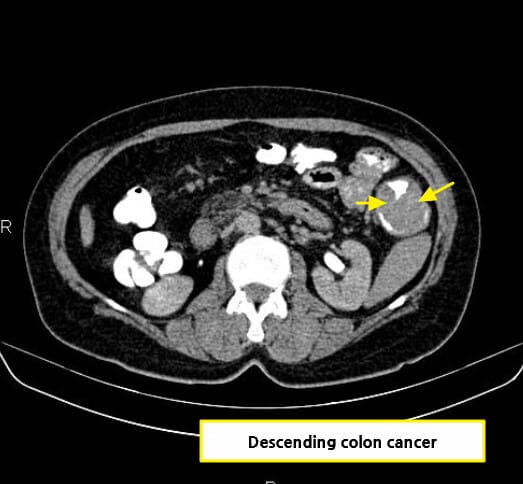

CT 소견 (Contrast-enhanced CT)

🔵 장벽 비후 (Bowel wall thickening)

암 부위의 장벽이 국소적으로 두꺼워지며, 조영증강되는 불균일한 덩어리로 관찰됩니다.

🔵 주위 지방 침윤

장 주변 지방조직에 염증 또는 종양 침윤이 퍼지며 음영이 흐려지는 소견입니다.

🔵 림프절 종대

단일 또는 다수의 림프절이 비대해져 전이 가능성을 시사합니다.

🔵 Annular constricting mass

암이 장을 원형으로 둘러싸며 협착을 유발하는 고전적 폐색 패턴입니다.

Di Muzio B, Colon adenocarcinoma. Case study, Radiopaedia.org (Accessed on 15 Jul 2025) https://doi.org/10.53347/rID-15157